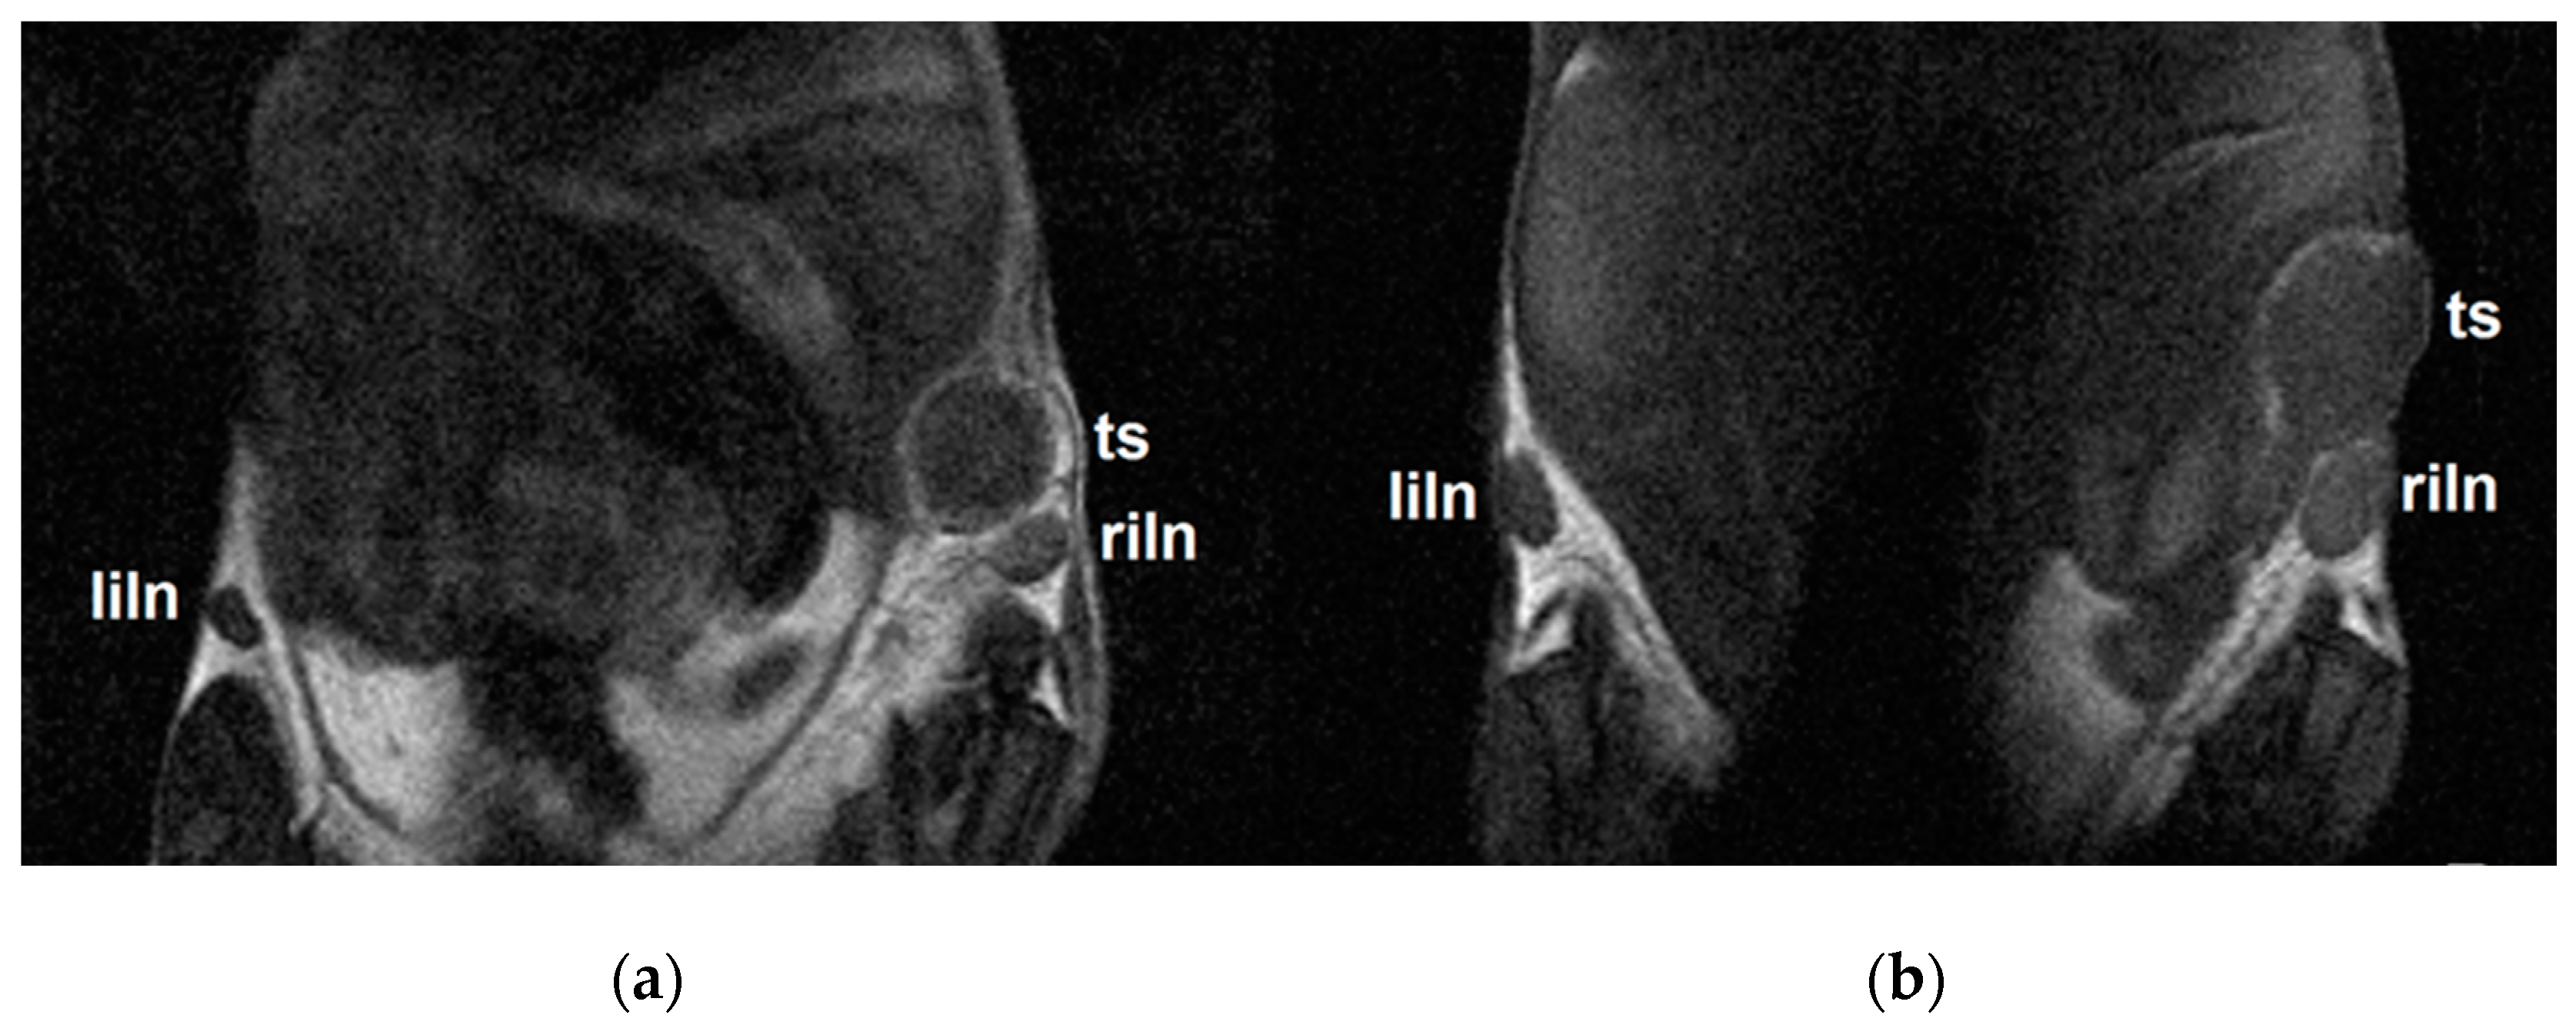

Figure 5.

Representative coronal MR images measured three days after the injection of (a) MN or (b) MNOX into the right thigh muscle. Left inguinal lymph nodes (liln), tumors (ts) and right inguinal lymph nodes (riln) represent sites of polymer accumulation.

As a complementary imaging method providing no attenuation of the signals in dependence to the tissue localization, we used a standard and non-invasive method routinely used both in experimental medicine and clinical practice: 1H-MRI. Focusing on three anatomical sites-both inguinal lymph nodes and respective tumors (Figure 5)-MRI confirmed the results obtained from fluorescence imaging, namely preferential polymer accumulation in SLNs, with significantly higher uptake in animals in the MN and MNOX groups compared to the DOT group (Figure 6). This analysis revealed the highest accumulation in both inguinal lymph nodes in the MN group. The highest accumulation of mannan-based polymer carriers was observed 4 h after injection in the MN group and 24 h after injection in the MNOX group, comparable to fluorescence results. Although mannan-based polymer carrier accumulation in tumors was less prominent than in SLNs, accumulation inside tumors peaked approx. one hour after mannan-based polymer carrier injection (Figure 6c).

The imaging efficacy of the lower-molecular-weight MN probe was significantly higher compared to the higher-molecular-weight MNOX probe (modifying the same mannan with polyoxazoline increases the molecular weight of the conjugate). This might indicate the predominance of the targeting effect of the mannan-DC-SIGN receptor interaction compared to the less effective solid tumor-targeting EPR effect, as evidenced by the molecular weight of the conjugates.